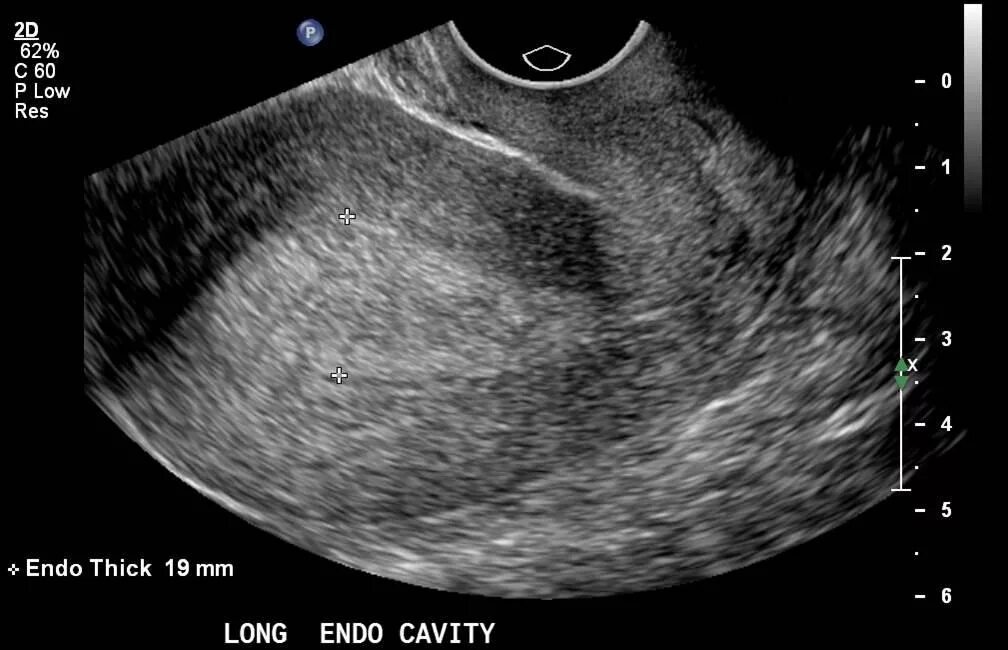

Гиперплазия эндометрия в постменопаузе узи. гиперплазия эндометрия в менопаузе на узи. атипическая гиперплазия эндометрия узи. атрофия эндометрия на узи.

Узи признаки опухоль эндометрия. карцинома эндометрия матки узи. аденокарцинома эндометрия узи. эндометрий в менопаузе по узи.

Ультразвуковые критерии гиперплазии эндометрия. гиперплазия эндометрия по узи. эндометрия в постменопаузе по узи.